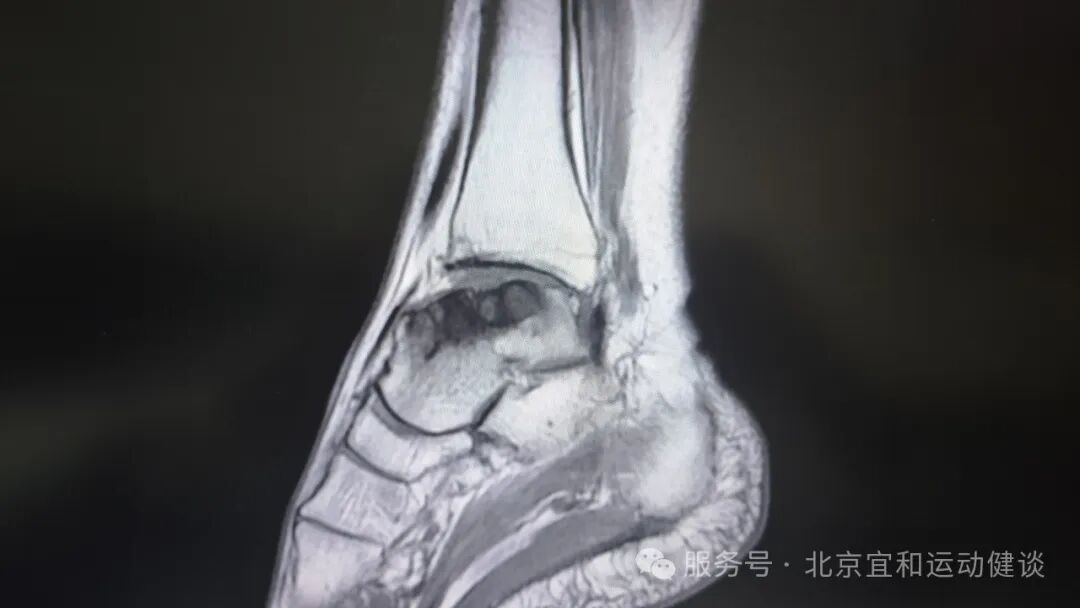

患者术后4周复查影像学资料